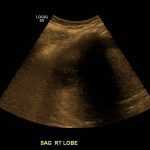

- Hepatomegaly with coarsened hepatic parenchymal echotexture

Hepatomegaly with coarsened hepatic parenchymal echotexture, concerning for cirrhosis.